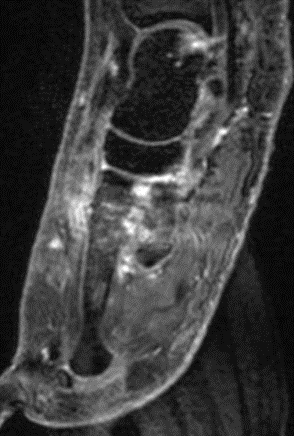

Nachfolgend 3 Fälle mit szintigraphisch nachweisbaren Tendinitiden in den Abbildungen 8.8., 8.9. und 8.10. Vergleichbare Fälle sind publiziert worden 697071.

Abbildung 8.8.a bis d: Patientin mit bekanntem Knick-Senk-Fuß. Anamnestisch Schmerzen in beiden Füßen, links > rechts seit ca. 2 Jahren. Fragestellung: Status der bekannten Fußwurzelarthrosen vor geplanter OP. Neben, unter anderem fortgeschrittenen Arthrosen im Naviculo-Cuneiforme-Gelenk, Nachweis einer Tibialis posterior-Sehnen-Tendinitis mit begleitender Periostitis/Ostitis am Malleolus postero-medial. Abbildung 8.8.a und b: in der Frühphase (2 Minuten nach Tracerinjektion) sind lineare Anreicherung des Tracers im Verlauf der linken Tibialis posterior Sehne zu sehen.  In der  Mineralisationsphase im SPECT/CT begleitende Periostitis/Ostitis am Malleolus postero-medial. Abbildung 8.8.c und d: Der Blick auf das CT im Weichteilfenster offenbart diffuse entzündliche Verdickungen im Verlauf der linken Tibialis posterior Sehne. Rechts unauffälliger Befund. Unten beispielhaft die schmerzhafte NC-Arthrose.

Abbildung 8.9. a bis c: Extern MRT-morphologisch V. a. Coalitio calcaneo-naviculare. Anamnestisch Schmerzen im linken OSG seit ca. 1,5 Jahren, gehäuftes „Umknicken“ des linken Fußes, Pes planus bds.. Abbildung 8.9.a zeigt die 3D-Früh-SPECT aus verschiedenen Blickwinkeln. Wie in Abbildung 8.8.a findet sich hier eine deutliche lineare Tracerakkumulation im Verlauf der linken Tibialis posterior Sehne. Abbildung 8.9.b: In der Mineralisationsphase wie auch im vorhergehenden Fall ossäre Reaktion postero-medial am Mallelolus medialis als Zeichen einer chronischen Tendinitis. Die Durchsicht der 7 Wochen zuvor angefertigten externen MRT bestätigte den Befund (er war leider nicht beschrieben worden). Im SPECT/CT wurde eine Coalitio ausgeschlossen.